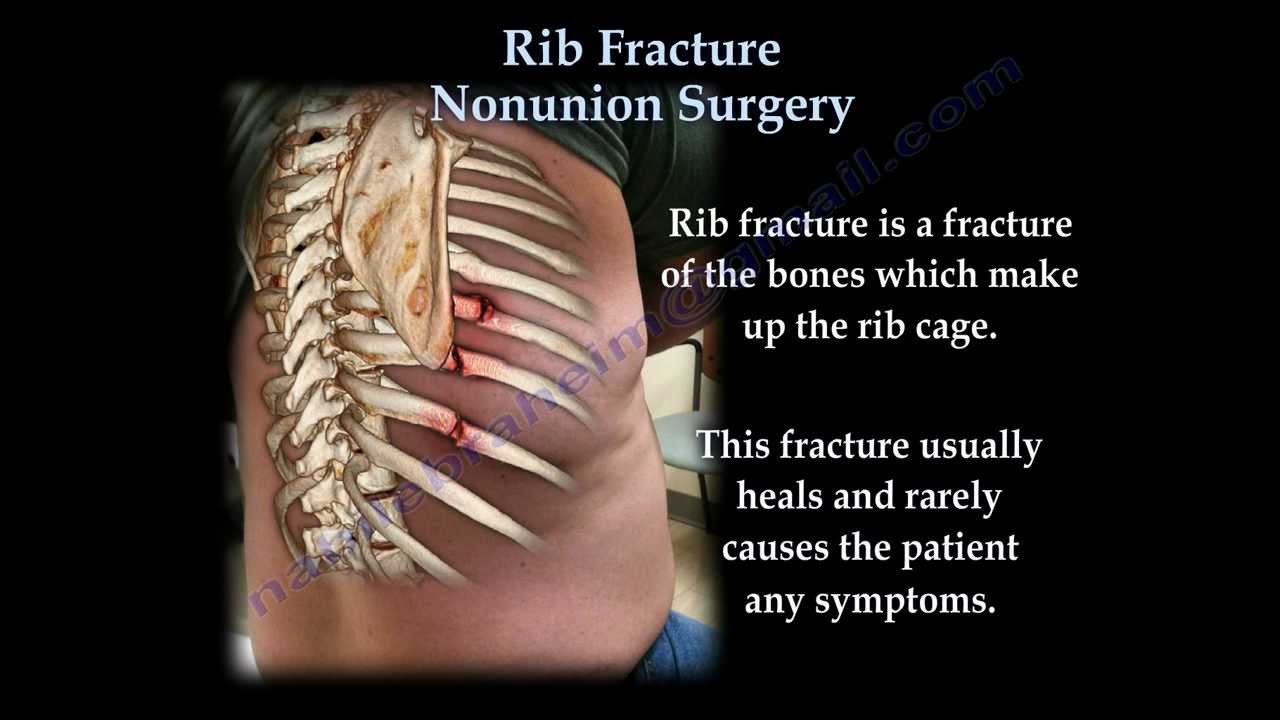

A broken rib typically causes sharp pain. To diagnose a rib injury, it’s best to see a medical professional who can look at your injuries with professional tools and technology. You may also feel or hear a crack or pop when the.

Sometimes, you may be able to feel a break in your rib by rubbing your finger over the rib. If you have a tender area on your ribs that hurts with every breath, you may have a broken rib. If you heard cracking during the injury or you hear or feel cracking when you move or.